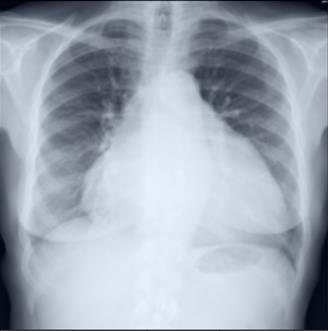

Thoracic disease detection from chest radiographs using deep learning methods has been an active area of research in the last decade. Most previous methods attempt to focus on the diseased organs of the image by identifying spatial regions responsible for significant contributions to the model's prediction. In contrast, expert radiologists first locate the prominent anatomical structures before determining if those regions are anomalous. Therefore, integrating anatomical knowledge within deep learning models could bring substantial improvement in automatic disease classification. This work proposes an anatomy-aware attention-based architecture named Anatomy X-Net, that prioritizes the spatial features guided by the pre-identified anatomy regions. We leverage a semi-supervised learning method using the JSRT dataset containing organ-level annotation to obtain the anatomical segmentation masks (for lungs and heart) for the NIH and CheXpert datasets. The proposed Anatomy X-Net uses the pre-trained DenseNet-121 as the backbone network with two corresponding structured modules, the Anatomy Aware Attention (AAA) and Probabilistic Weighted Average Pooling (PWAP), in a cohesive framework for anatomical attention learning. Our proposed method sets new state-of-the-art performance on the official NIH test set with an AUC score of 0.8439, proving the efficacy of utilizing the anatomy segmentation knowledge to improve the thoracic disease classification. Furthermore, the Anatomy X-Net yields an averaged AUC of 0.9020 on the Stanford CheXpert dataset, improving on existing methods that demonstrate the generalizability of the proposed framework.